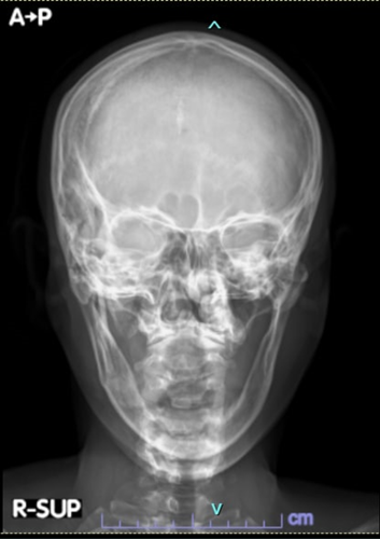

Role of FGF23 and alkaline phosphatase in bone health: Case-based clinico-physiologic discussion

Proper bone development requires the coordinated and calibrated action of various cells, hormones, enzymes and nutrients. In this paper, we present two clinical cases of metabolic bone disorders – one with excessive fibroblast growth factor-23 (FGF23) and the other, with low alkaline phosphatase. FGF23 and alkaline phosphatase are not-so-well-known players in bone health. This paper puts the spotlight on these two, and discusses their role in bone development, and how abnormal levels lead to disease.